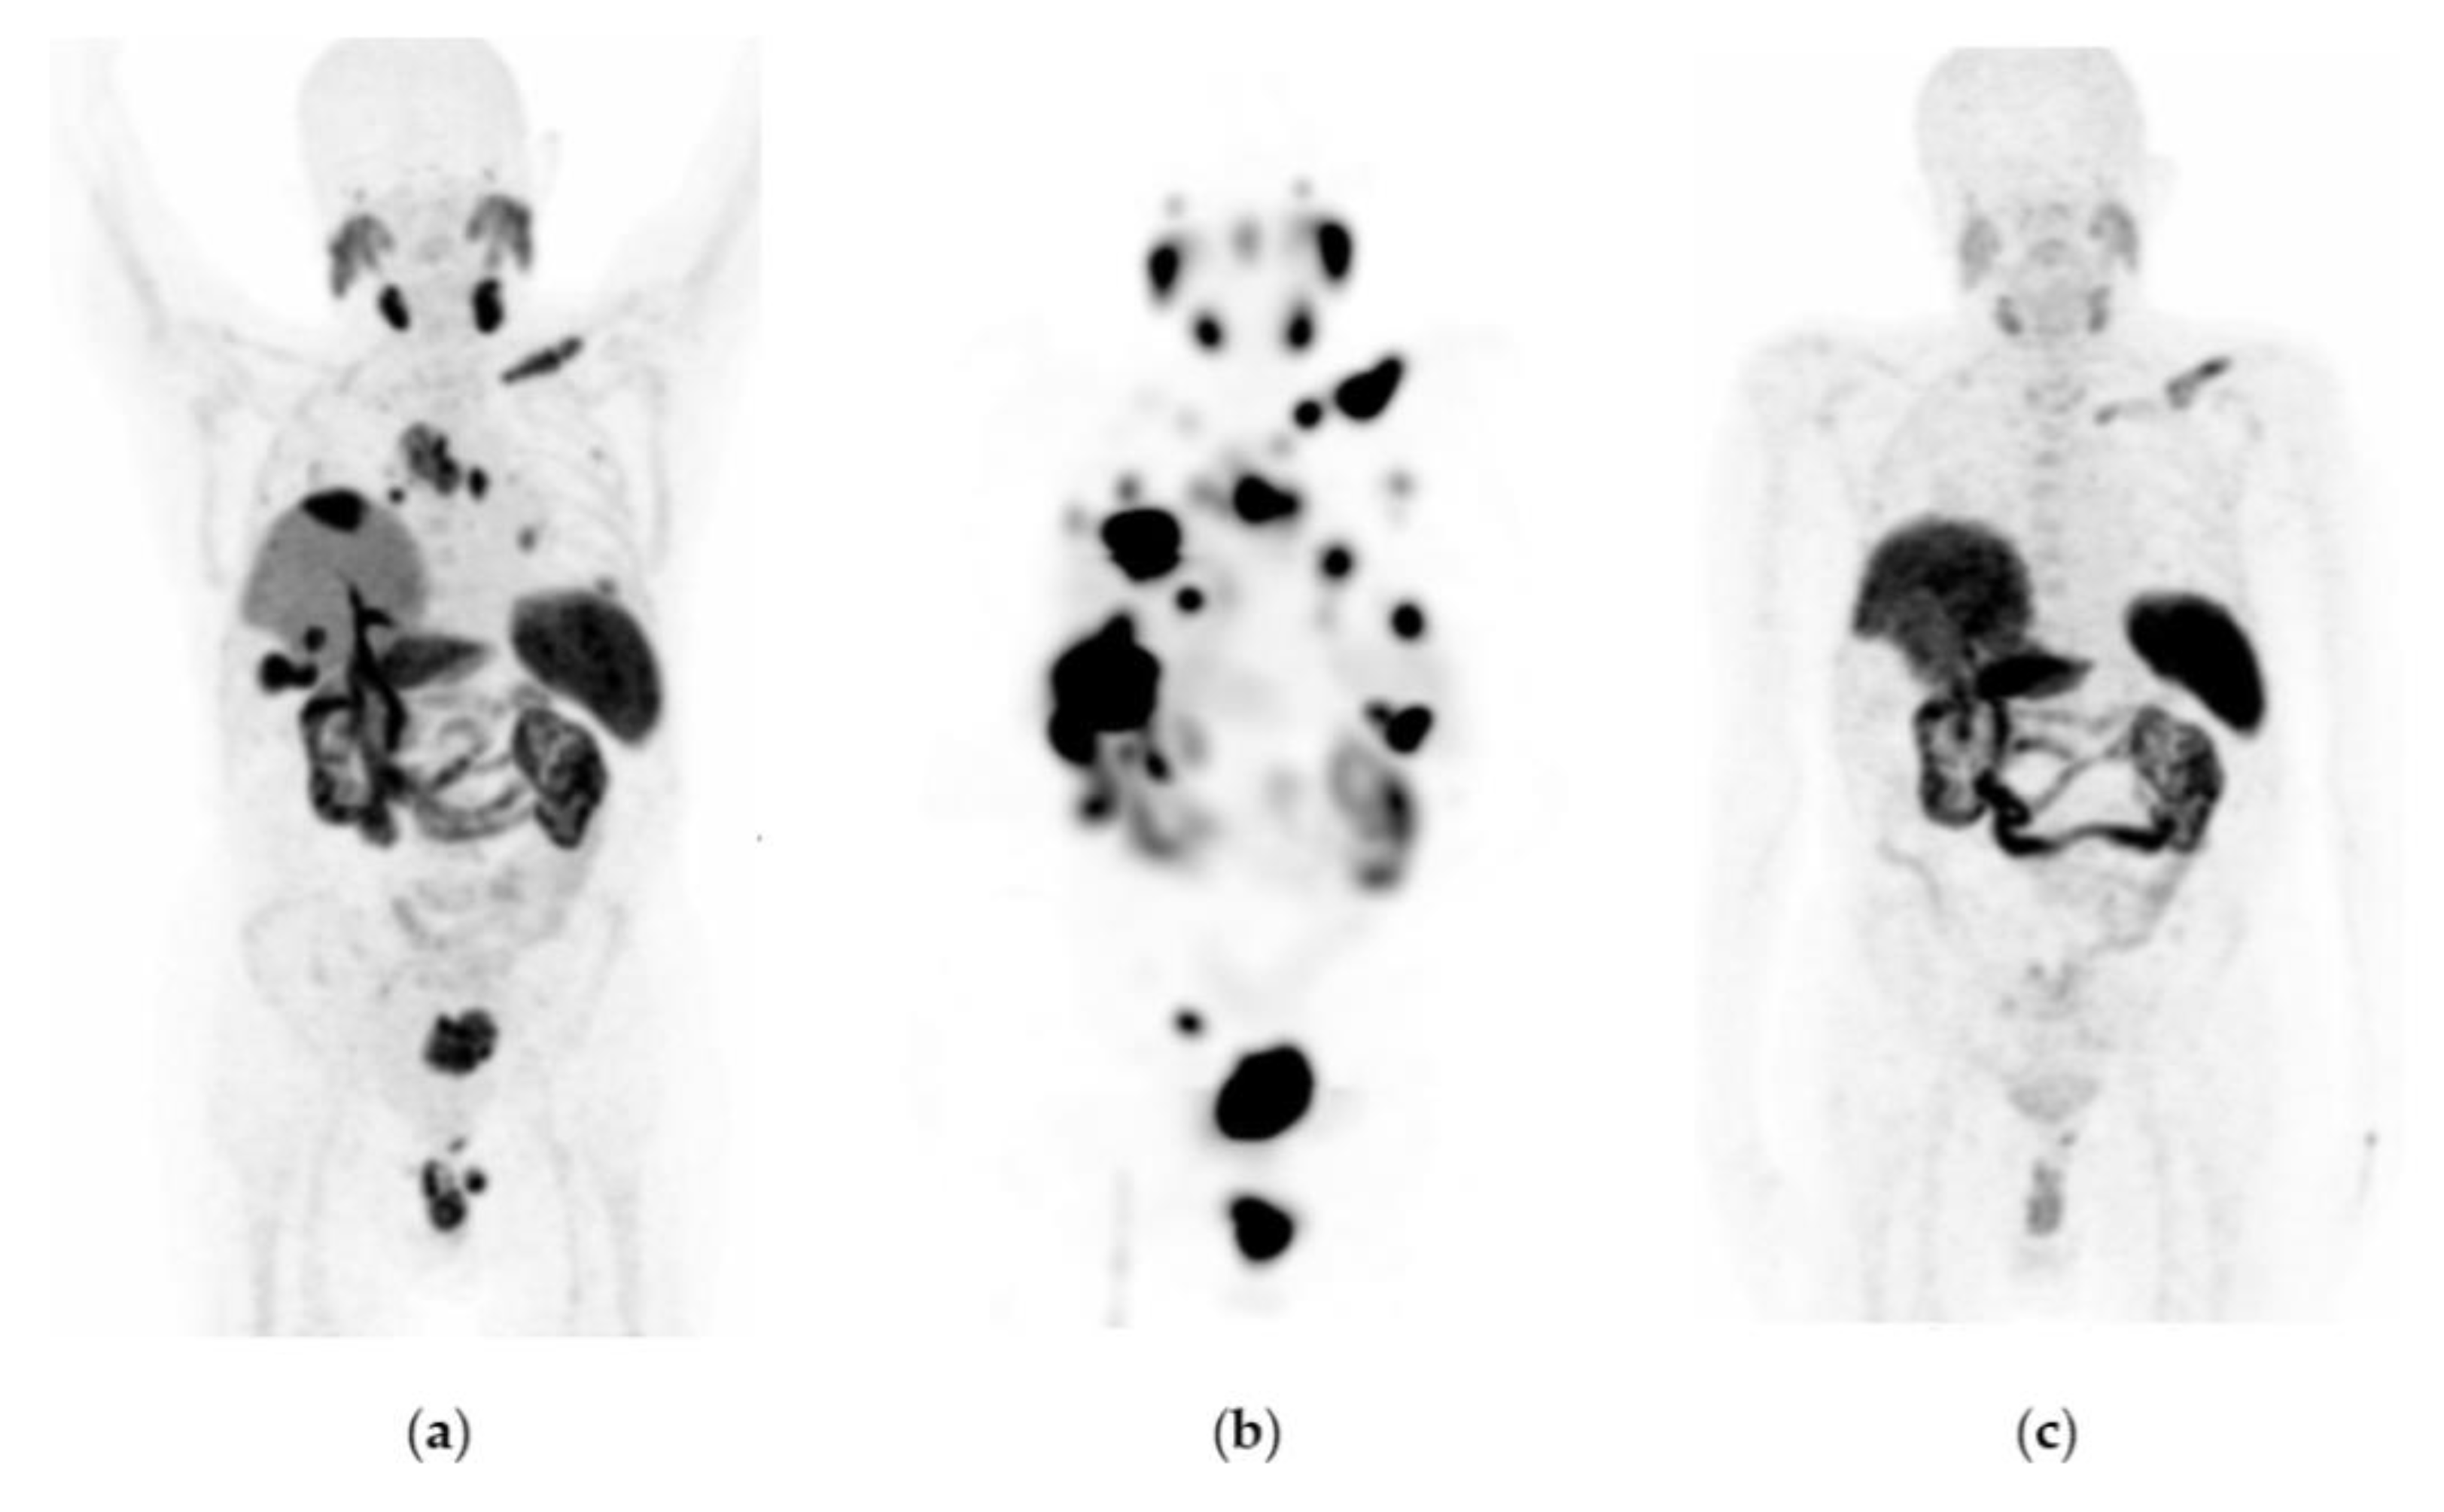

Figure 3. Patient with progressive and metastatic castration-resistant prostate cancer (mCRPC): (a) 68Ga-iPSMA PET/CT imaging before 177Lu-iPSMA therapy; initial levels of hemoglobin (11.1 g/dL), leucocytes (4900/µL), creatinine (0.88 mg/dL), platelets (115,000/µL), and serum PSA (84.7 ng/mL). (b) 177Lu-iPSMA SPECT imaging (first dose). (c) 68Ga-iPSMA PET/CT imaging 10 months after the first 177Lu-iPSMA dose was administered; levels of hemoglobin (10.1 g/dL), leukocytes (2100/µL), creatinine (0.91 mg/dL), platelets (87,000/µL), and serum PSA (7.7 ng/mL). The patient responded partially to 177Lu-iPSMA therapy (four doses every six weeks; 7.4 GBq/dose).

177Lu-iPSMA showed an overall response rate of 36.6% (Table 2). Figure 2 and Figure 3 show typical clinical cases of complete response (disappearance of all lesions or adenopathies less than 10 mm short axis) and partial response (decrease of at least 30% in the sum of the largest diameters of lesions compared with the baseline study) after 177Lu-iPSMA therapy. In addition, the reduction of large tumors and multiple metastatic lesions are proof of the high specificity and molecular recognition of 177Lu iPSMA by PSMA at the tumor cell level (Appendix A) (Figure A1, Figure A2 and Figure A3).

Patients with mPC who received three to five doses of 177Lu-iPSMA showed an overall survival of 660 days (21.7 months) (Table 2; Figure 1a) with decreased radiotracer tumor uptake (SUV) and PSA level in 80% (n = 33) and 73% (n = 30) of the subjects, respectively (Table 2). Specifically, 52% of cases had a PSA decline of >50% after completing treatment.

The hazard ratio was 0.5650 (95% CI: 0.3391–0.9412), indicating a 43.5% reduction in the risk of death in favor of the 177Lu-iPSMA group (Table 2). In addition, 50% of patients were free of progression at 323 d (10.6 months) after treatment (Figure 1b).